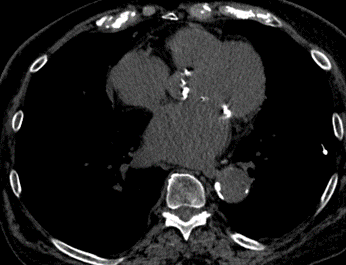

Left atrium enlargement

The diameter measurements of the left atrium on CT axial images should be determined as the largest anterior-posterior diameter. It is a continuous, metric variable.